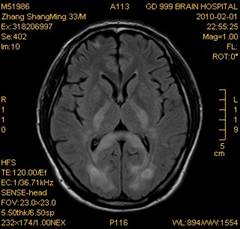

案例1 患者,男,33岁, 海洛因脑病的头颅MR。表现为双侧大脑后部皮层下白质、双侧内囊后肢、枕叶白质、胼胝体压部、中脑、桥脑、双侧小脑半球齿状核质及双侧桥臂多发对称性片状及斑片状长T1长T2异常信号影,FLAIR序列呈高信号,其中双侧内囊后肢表现为特异的“八字征”,双侧小脑半球齿状

核质表现为对称的“蝶翼征”,脑干病变呈“蟹钳征”及“中空征”。增强后双侧半卵圆中心、双侧枕叶白质及双侧小脑半球病变内或边缘中度强化影。给予患者抗炎、脱水、疏通血管及营养神经等药物治疗,一个月后痊愈出院。